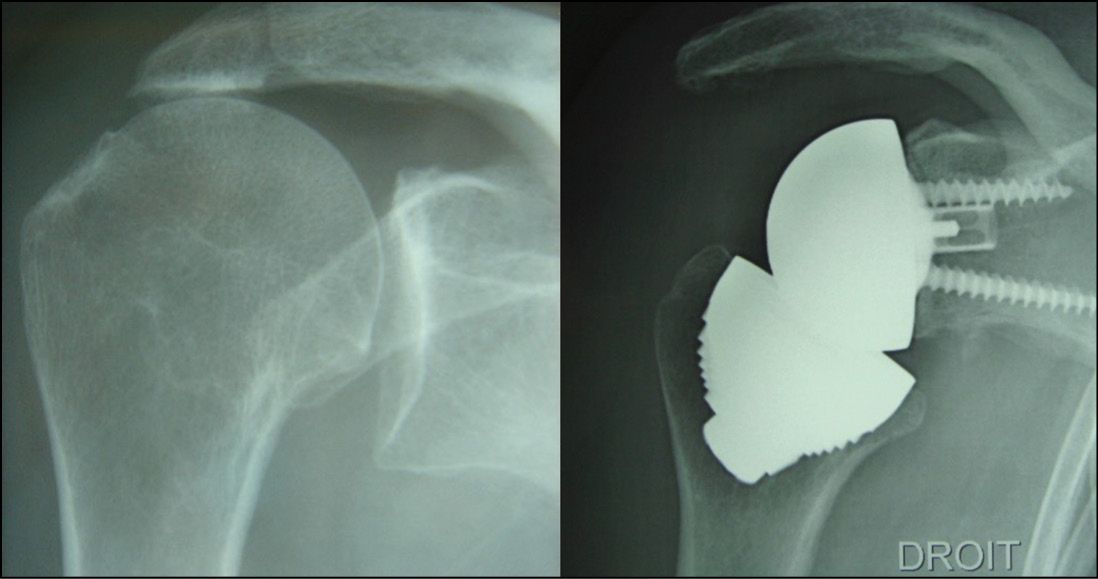

Malunion of the proximal humerus, if recent enough to have not affected the glenoid cartilage, is again a good indication: a stemless humeral implant makes it possible to restore the humeral head without any of the constraints caused by offsets or tuberosity transfer (Fig. 11).[4] Ballas R, Teissier P, Teissier J. Stemless shoulder prosthesis for treatment of proximal humeral malunion does not require tuberosity osteotomy. Int Orthop. 2016; 40:1473-9. doi: 10.1007/s00264-016-3138-y.